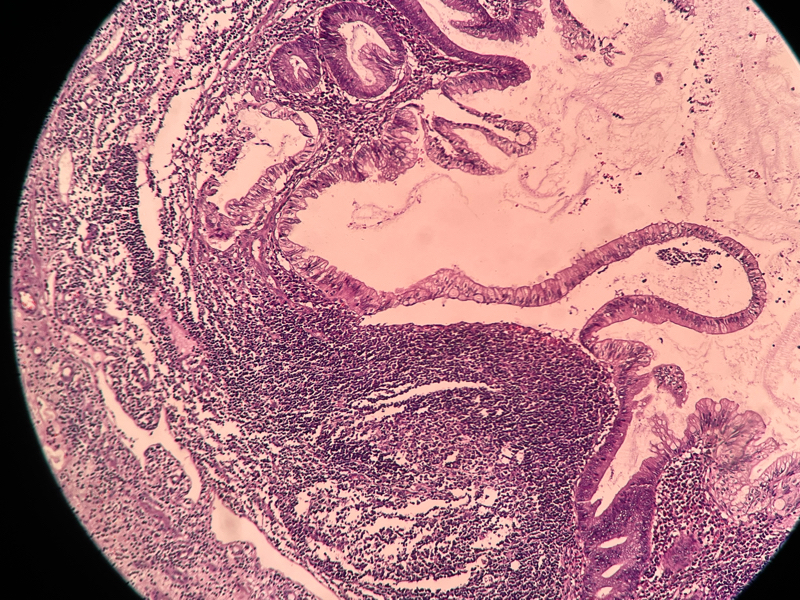

性别

女

年龄

54

临床诊断

急性阑尾炎

一般病史

持续性右下腹痛8小时

标本名称

阑尾

大体所见

阑尾约7.1cm ,直径约1.0-1.2,局部有脓苔

请各位老师看下这有没有问题,担心漏诊

化脓性阑尾炎。